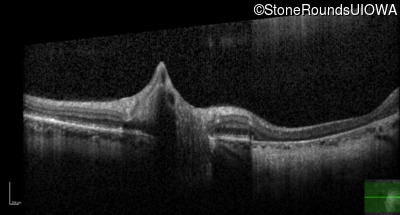

Optical Coherence Tomography - Right - 20/20 sc

Exemplar / OCT Stack